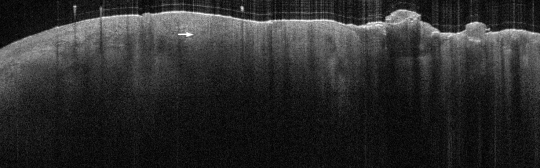

VA109: Left Dorsal Hand, Squamous Cell Carcinoma, Keratoacanthoma Type

- Note absence of collagenous texture in lower scan area

VA109: Left Dorsal Hand, Adjacent, Normal